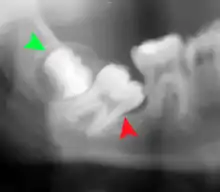

Impacted wisdom teeth are classified by the direction and depth of impaction, the amount of available space for tooth eruption, and the amount of soft tissue or bone (or both) that covers them. The classification structure helps clinicians estimate the risks for impaction, infections and complications associated with wisdom teeth removal.[6] Wisdom teeth are also classified by the presence (or absence) of symptoms and disease.[7]

One review found that 11% of wisdom teeth will have evidence of disease and are symptomatic, 0.6% will be symptomatic but have no disease, 51% will be asymptomatic but have disease present and 37% will be asymptomatic and have no disease.[7] Impacted wisdom teeth are often described by the direction of their impaction (forward tilting, or mesioangular being the most common), the depth of impaction and the age of the patient as well as other factors such as pre-existing infection or the presence of pathology (cysts, tumors or other disease).[5]:143–144 Each of these factors is used to predict the difficulty (and rate of complications) when removing an impacted tooth, with age being the most reliable predictor[8] rather than the orientation of the impaction.[9]

Coronectomy is a procedure where the crown of the impacted wisdom tooth is removed, but the roots are intentionally left in place. It is indicated when there is no disease of the dental pulp or infection around the crown of the tooth, and there is a high risk of inferior alveolar nerve injury.[31]